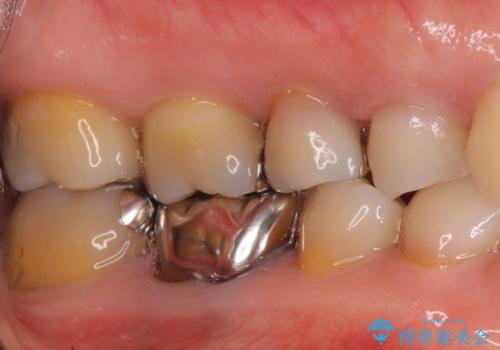

- 虫歯治療を希望して来院。

保険適用の銀色のつめもののやり替えを行いました。

- 30.8万円(右上4567 emaxプレスインレー 7万円x4本)費用は治療当時の料金となります